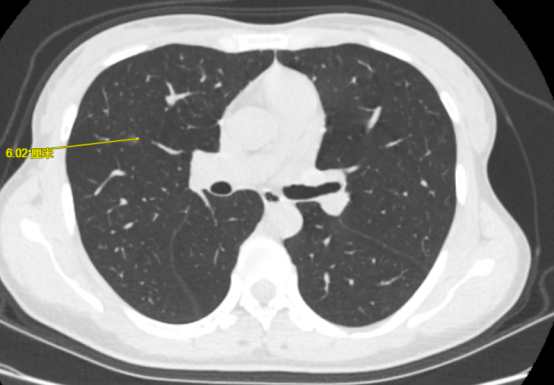

王女士(化名),两年前体检发现有肺磨玻璃结节,医生建议她规律复查胸部CT观察病灶变化情况。

图片

图中红圈内为该患者肺磨玻璃病灶

半个月前,她复查胸部CT发现肺内结节较前增大,进一步做了PET-CT检查,考虑原位或微浸润癌可能大。